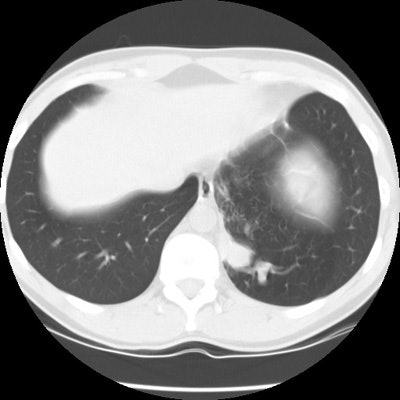

The patient below presented for evaluation of an abnormal CXR which demonstrated a left retrocardiac mass. (Click image to enlarge)

CT scan revealed a soft tissue mass in the left posterior-medial lung which had a branching tubular appearance. Some associated para-emphysematous changes were noted. (Click images to enlarge)